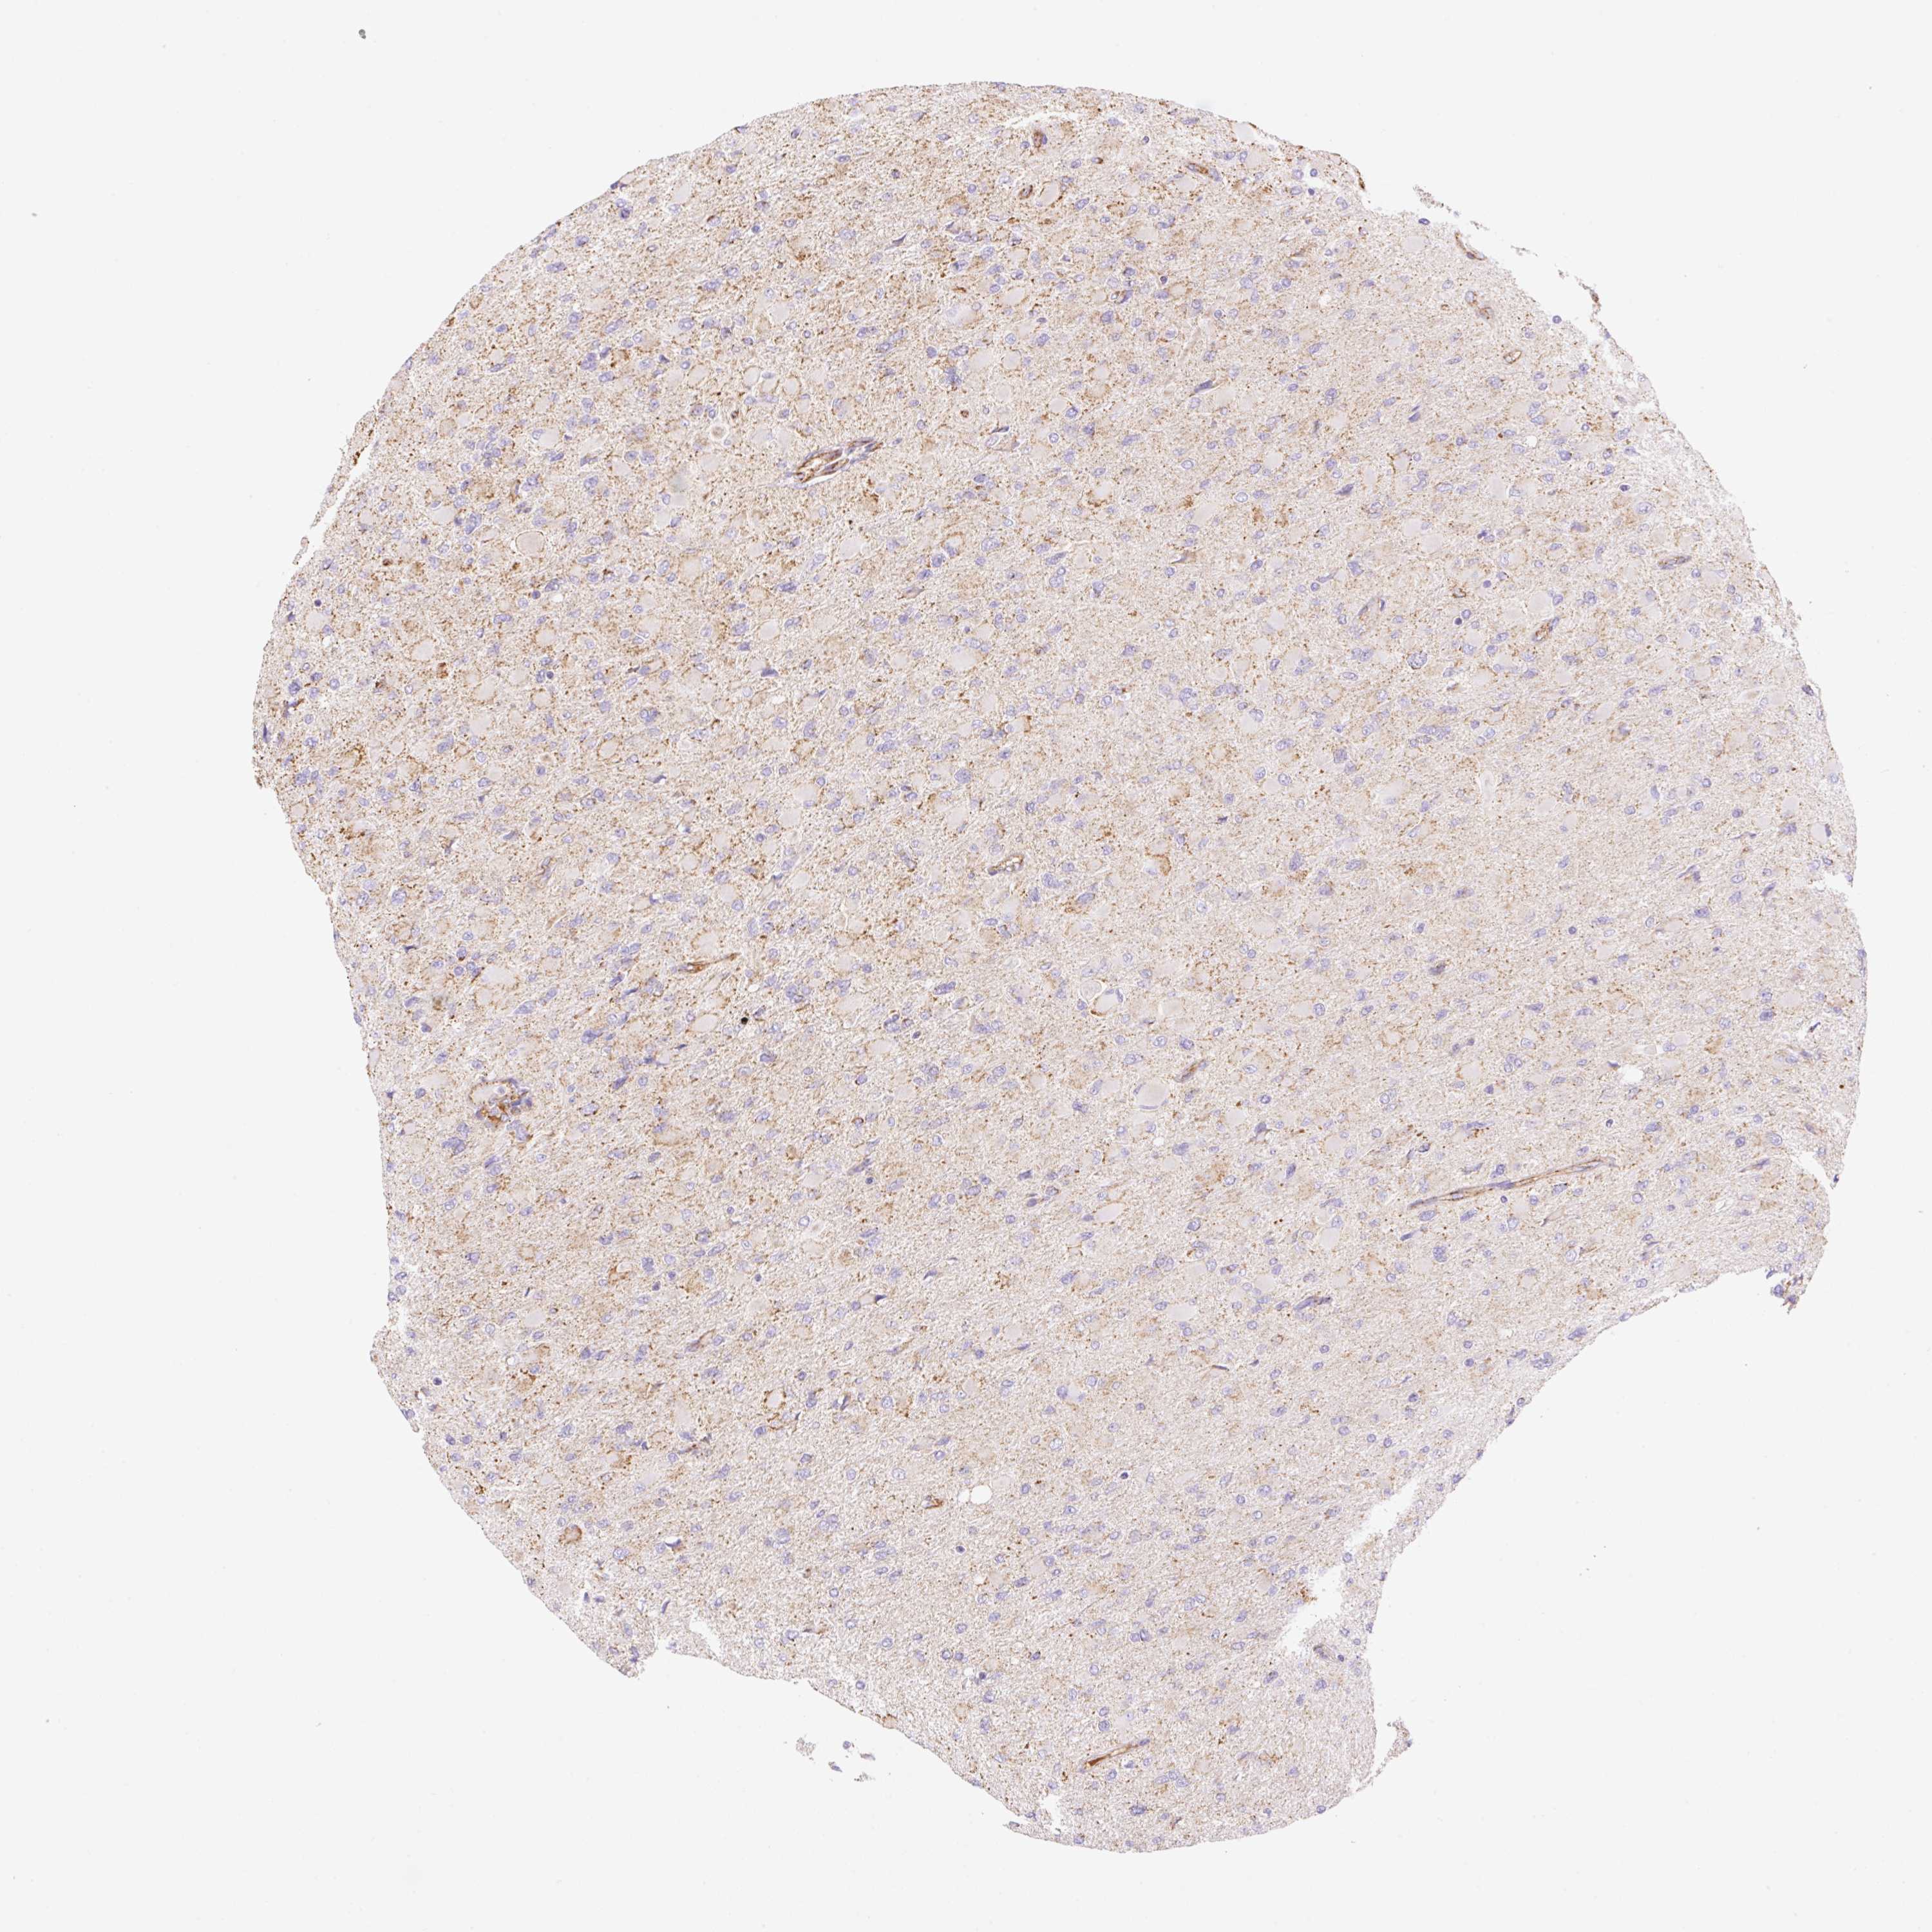

GLIOMA - Protein expressioni

A mouse-over function shows sample information and annotation data. Click on an image to view it in a full screen mode. Samples can be filtered based on level of antibody staining by selecting one or several of the following categories: high, medium, low and not detected. The assay and annotation is described here.

Note that samples used for immunohistochemistry by the Human Protein Atlas do not correspond to samples in the TCGA dataset.

Antibody stainingi

Antibody staining in the annotated cell types in the current human tissue is reported as not detected, low, medium, or high, based on conventional immunohistochemistry profiling in selected tissues. This score is based on the combination of the staining intensity and fraction of stained cells.

Each image is clickable and will lead to virtual microscopy that enables deeper exploration of all samples and also displays staining intensity scores, fraction scores and subcellular localization as well as patient and tissue information for each sample.

Antibody HPA056293

Staining

High

Medium

Low

Not detected

Intensity

Strong

Moderate

Weak

Negative

Quantity

>75%

75%-25%

<25%

None

Location

Nuclear

Cytoplasmic/membranous

Cytoplasmic/membranous,nuclear

Glioma, malignant, High grade